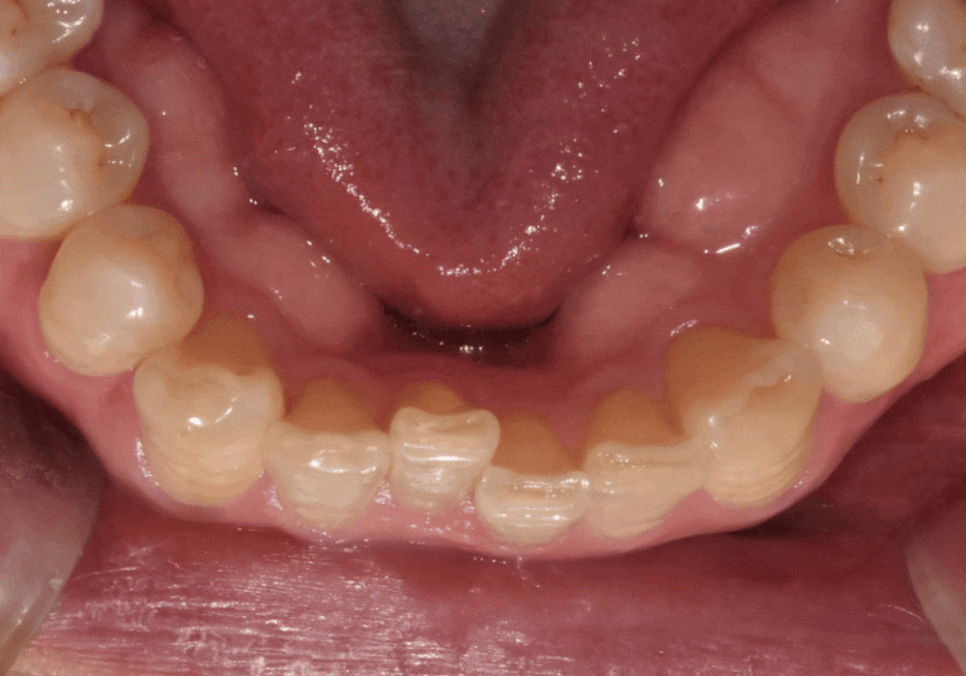

이번 사례의 환자분은

아래 중앙 앞니(#41) 하나가

혼자만 안으로 쑥 들어가 있어

배열이 어긋나 보이는 게

가장 큰 고민이셨습니다.

230613

치아 라인을 위에서 내려다보니

매끄러운 U자 아치형이

앞니로 인해

'ㄷ' 자로 꺾인 모습이었습니다.